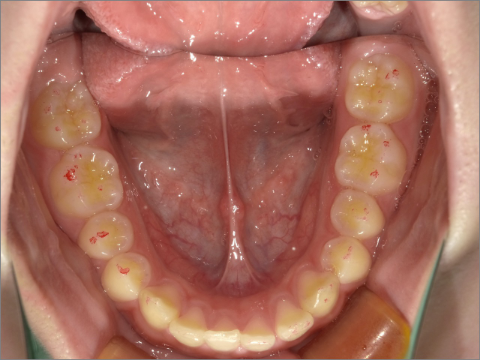

ご年齢 15歳女性

治療期間 2022/07/02〜2023/12/02(1年5ヶ月)

診断 110,000円(税込)

アライナー 660,000円(税込)

リテーナー 55,000円(税込)

BEFORE

AFTER